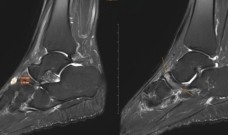

Sau phẫu thuật, bệnh nhân được túi giãn da vùng da đầu có tóc. (Ảnh: BVCC)

Sau khi hội chẩn liên chuyên khoa, các bác sĩ đã lựa chọn phương án đặt túi giãn da vùng da đầu có tóc, sau đó kết hợp vá sọ bằng lưới titan và chuyển vạt da giãn để che phủ toàn bộ vùng khuyết.

Tháng 11/2025, bệnh nhân được phẫu thuật đặt túi giãn da 450cc tại vùng thái dương. Túi giãn được bơm định kỳ nhằm tăng dần diện tích da đầu có tóc, chuẩn bị cho giai đoạn tạo hình tiếp theo.

Đến tháng 1/2026, bệnh nhân được thực hiện phẫu thuật: Vá màng sọ bằng lưới titan, cắt bỏ sẹo giãn diện rộng 90 cm², lấy túi giãn và chuyển vạt da đầu có tóc che phủ toàn bộ vùng khuyết.